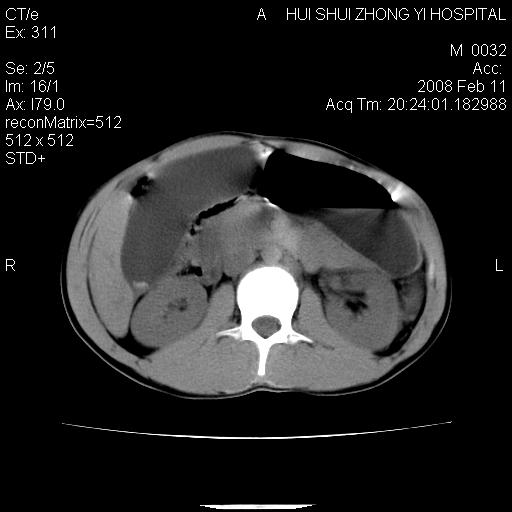

8年前曾在贵洲省人民医院b超诊断为肝内胆管结石。现腹痛剧烈,现发烧、头痛、恶心呕吐县医院b超示胆囊肿大大小159*46mm,囊内见6*5mm强回声光团,胆各总管内径56mm。提示:胆囊结石、急性胆囊炎、胆总管重度扩张。

胆囊结石.急性胆囊炎.重度胆管扩张.右侧胸腔少量积液,建议ct增强

考虑先天性胆管囊肿;胆囊增大并结石。右侧胸腔少量积液,建议ct增强。

caroli囊肿并囊内结石。胆囊增大并胆结石。典型!

先天性胆管囊肿,胆囊结石、胆囊增大,右侧少量胸腔积液。